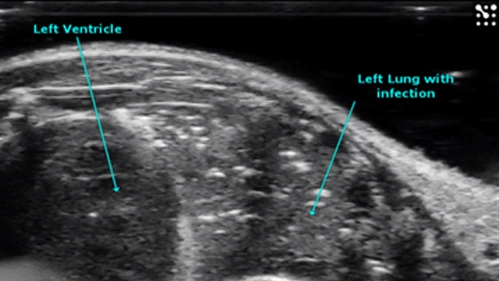

Diseased Lung

Lung infection can be detected and compared to healthy lung tissue.